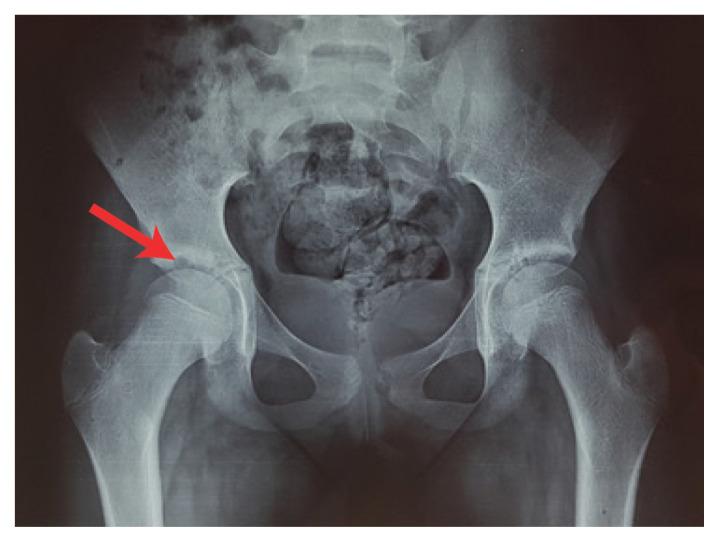

Chronic recurrent multifocal osteomyelitis (CRMO) is an auto-inflammatory disease characterised by sterile bone lesions. We report a case of a seven-year-old female patient who presented at a university hospital in 2010 and 2018 with CRMO. While the most promising results have been observed in patients under treatment with bisphosphonates (BPs), the initial decision to treat the current patient with a dose of zoledronic acid every six months was recalled as the patient developed tonic-clonic seizures immediately following the second dose BP administration. Following recall, the patient maintained a prompt response at follow-up and her disease remained controlled with non-steroidal anti-inflammatory drugs. The current case report speculates a possible relationship between BP use and a possible seizure threshold reduction, thereby emphasising the need for closer monitoring when BPs are used.

慢性复发性多灶性骨髓炎(CRMO)是一种以无菌性骨病变为特征的自身炎症性疾病。我们报告了一例 7 岁女性患者,她于 2010 年和 2018 年在一所大学医院就诊,患有 CRMO。虽然在接受双膦酸盐(BPs)治疗的患者中观察到了最有希望的结果,但由于在第二次 BP 给药后患者立即出现强直-阵挛性发作,最初决定用唑来膦酸对当前患者进行每六个月一次的治疗剂量被召回。召回后,患者在随访中保持了快速反应,并且她的疾病仍然用非甾体抗炎药控制。本病例报告推测 BP 使用与可能的癫痫发作阈值降低之间可能存在关系,从而强调了在使用 BPs 时需要更密切的监测。